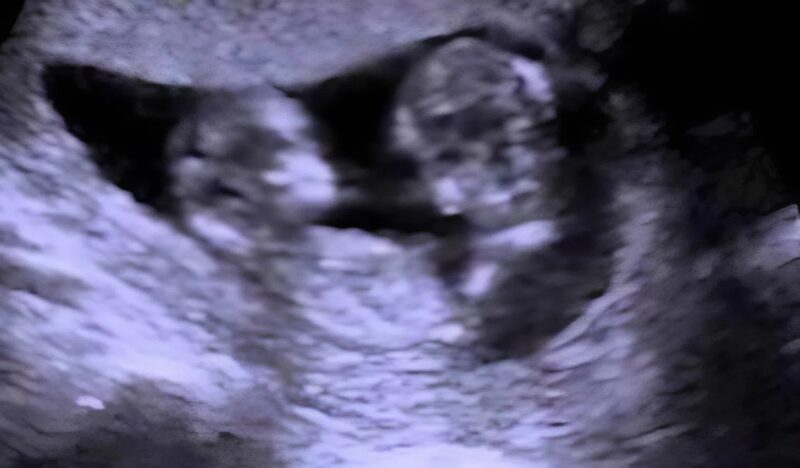

When the day of the ultrasound arrived, Julia lay on the table, heart pounding with excitement . The doctor stared at the screen in silence for what felt like forever. Then, in a calm, almost indifferent voice, she said something that made Julia’s blood run cold:

“Here are two heads… two babies… they’re lying face to face… but wait— they’re not hugging. They’re connected.”

Julia froze. Her smile disappeared as the doctor explained that the babies were conjoined at the abdomen, sharing a small part of their liver and the abdominal wall. Though they were developing normally, this tiny fusion could become a huge problem later.